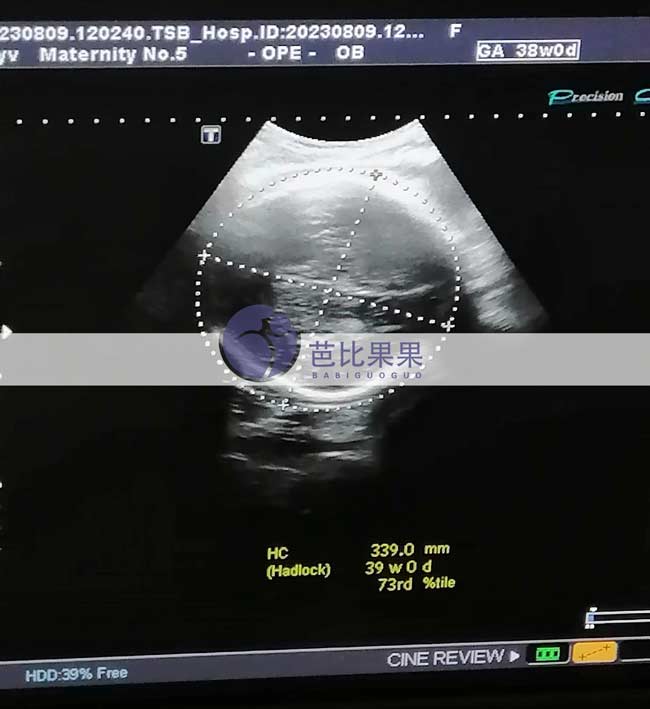

P女士的乌克兰试管妈妈孕38周B超依然美丽

P女士家的乌克兰试管妈妈已经孕38周到医院做B超,从孕初期美到孕晚期,真的有孕妈一直不会变丑哦